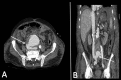

Aortocaval fistula (ACF) is a rare complication of abdominal aortic aneurysms (AAA), involving less than 1% of all AAA and is associated with high morbidity and mortality; it is even more uncommon, following endovascular aneurysm repair. The clinical presentation can be variable and making the diagnosis can be difficult. It can present with symptoms and signs of an abdominal emergency or systemic hypoperfusion. The traditional method of repair has been open surgery, which is associated with a high mortality rate. Endovascular repair has become more common, but results are difficult to interpret due to the low incidence of ACF. A high index of suspicion is imperative to avoid delay in diagnosis and care.